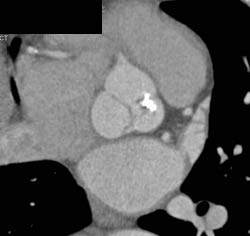

Diseased Leaflet Aortic Valve